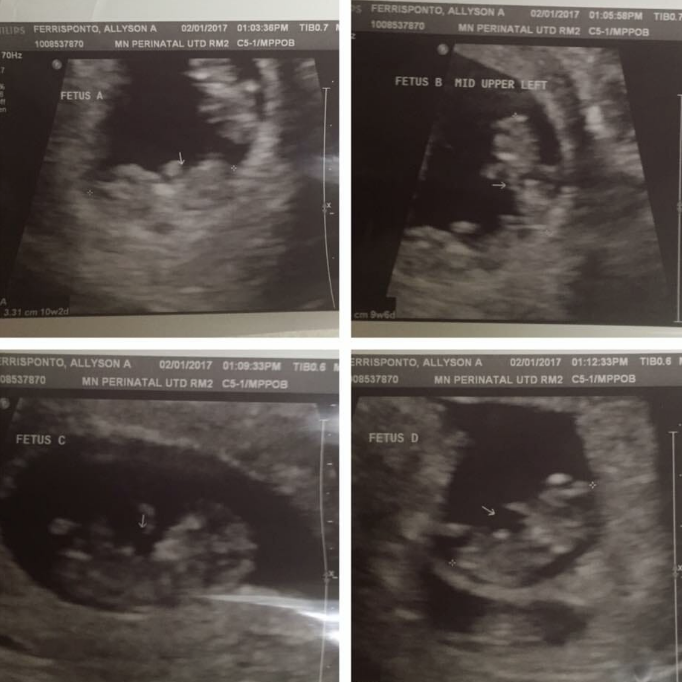

Rutin kontroller için eşiyle beraber doktora gittiklerinde hayatlarının en büyük sürpriziyle karşılaştılar. Ultrasonda bir değil, iki değil, üç değil tam dört bebek görüldü. 39 yaşındaki Allyson’ın dördüzleri olacaktı! Allyson, US Magazine’e “Dört bebeğim olacağını öğrenince sevinçten ağlamaya başladım. Tek isteğim bir an önce anne olmaktı” dedi.